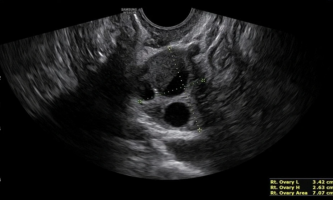

Endometrioma con evidencia del característico doble nivel líquido-líquido

Dentro de la formación, se pueden observar puntos hiperecogénicos, síntoma de acumulación de hemosiderina (fig1).